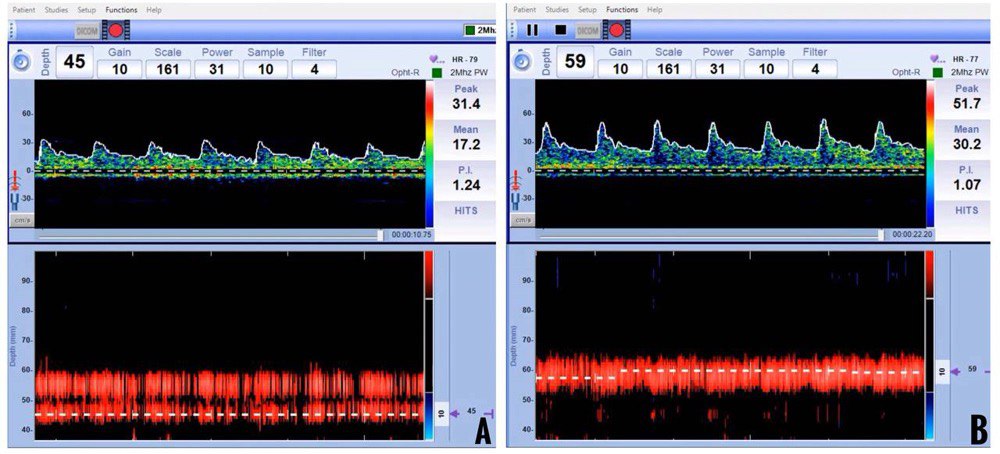

The PI is inversely proportional to intracranial compliance and CBF. Hence, factors affecting CBF, such as age, sex, PaCO2, and arterial blood pressure, also affect PI. Normal values of PI range from 0.5 to 1.19 (Figure 10). Values of PI less than 0.5 are seen in conditions like arteriovenous malformations, stenosis in the proximal vessels, and hypercapnia. Values of PI more than 1.2 are seen in conditions like raised ICP, stenosis in the distal vessels, and hypocapnia. Although an increase in PI has been used as an indirect measure of raised ICP, one has to remember that it is not specific due to various confounders (Figure 11).8

Figure 10: Normal (A) and high (B) Pulsatility Index spectral waveforms

Figure 11: Increased Pulsatility Index (PI) in hypotension with impaired cerebral autoregulation (A) and raised intracranial pressure (B).